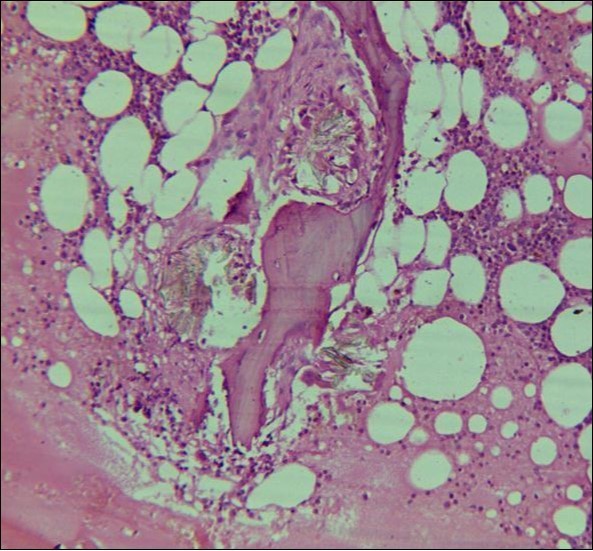

A 24 years old male, presented with the complaints of multiple recurrent renal stones bilaterally. He was on dialysis since last 6 months. His brother had died with chronic renal insufficiency secondary to nephrolithiasis. His routine investigations at the time bone marrow studies revealed anemia with a Haemoglobin of 6.6g/dl, White blood cell count of 5.3 x 109/l; Platelet count of 228 x 109/l. Serum Creatinine was very high 13.9mg/dl. X Ray Abdomen revealed multiple bilateral renal calculi and in addition gall bladder calculi. On ultrasound abdomen his right kidney was 10.5cm x 5.6 cm, had a cyst in the upper pole, multiple calculi were causing hydronephrosis. Left kidney was 8.5cm x 4.8 cm, with multiple calculi. Both kidneys showed increased echogenecity. Serum oxalate levels were 91.2 mg/dl (Normal Range 1-2.4 mg/dl). His Parathyroid MIBI scan was normal, but plasma Parathyroid hormone levels were 373 pg/ml (Normal Range 16 – 87pg/ml). Normochromic normocytic anaemia was present, with normal WBC and platelet count. The bone marrow aspirate was unsuccessful. The trephine biopsy revealed reduced cellularity, depressed erythropoeisis with partly replaced haemopoietic tissue with calcium oxalate crystals (Figure 4) which showed birefringence on polarized light (Figure 5).

Figure 4.Photomicrograph of bone marrow core from case2 showing Para trabecular arrangement of calcium oxalate crystals. Increased fat spaces and depressed erythropoiesis is evident.